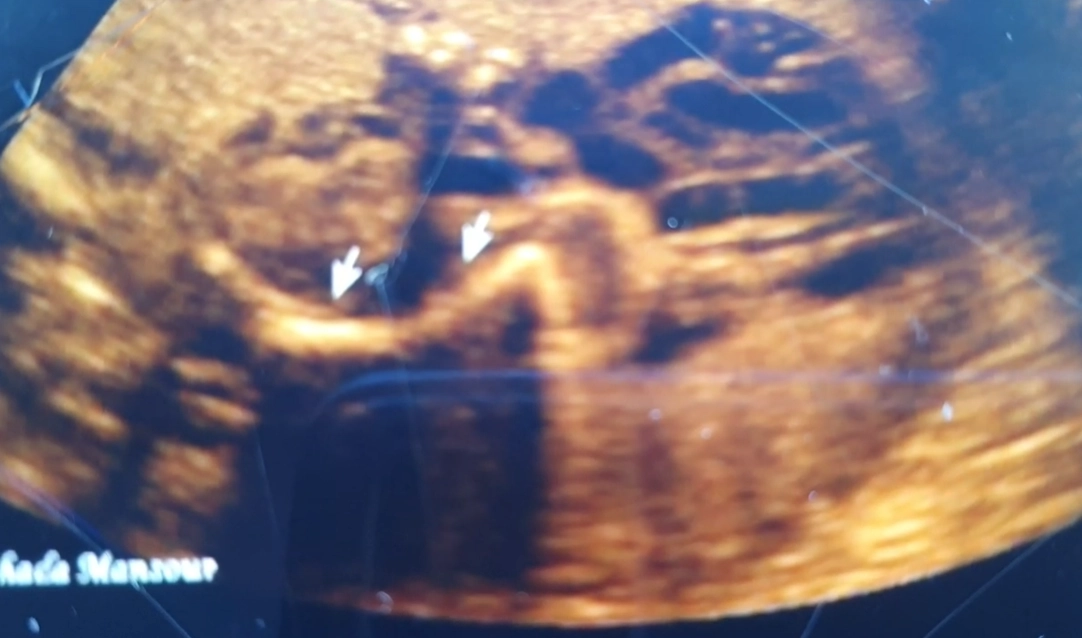

• XII. Hệ cơ xương khớp thai nhi

• Giải phẫu siêu âm cơ xương khớp quý I

• Loạn sản xương quý I (Skeletal dysplasias)

• Cơ xương khớp thai

• Tổng quan CXK

• Tổng quan cơ xương khớp thai nhi (Approach to fetal skeletal)

• Chẩn đoán phân biệt

• Ngắn nhẹ xương đùi / xương cánh tay thai (Mildly Short Femur / Humerus)

• Xương cong ở thai nhi (Curved / Angulated Bones)

• Bất thường cốt hóa thai (Abnormal Ossification)